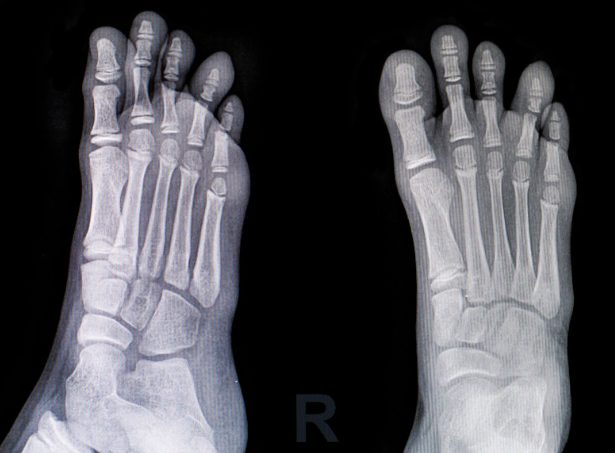

診断

診察とレントゲンなどで診断します。仰臥位で患肢を屈曲すると患肢が開排(外転・外旋)していくドレーマン徴候を呈します。

単純X線正面像で骨端線が不鮮明にみえます。すべりが進行すると骨端が内側に位置するTrethowan(トレソーワン)徴候、側面像では骨端核後方部分が寛骨臼の外にはみ出すCapener(ケイプナー)徴候を認めます。